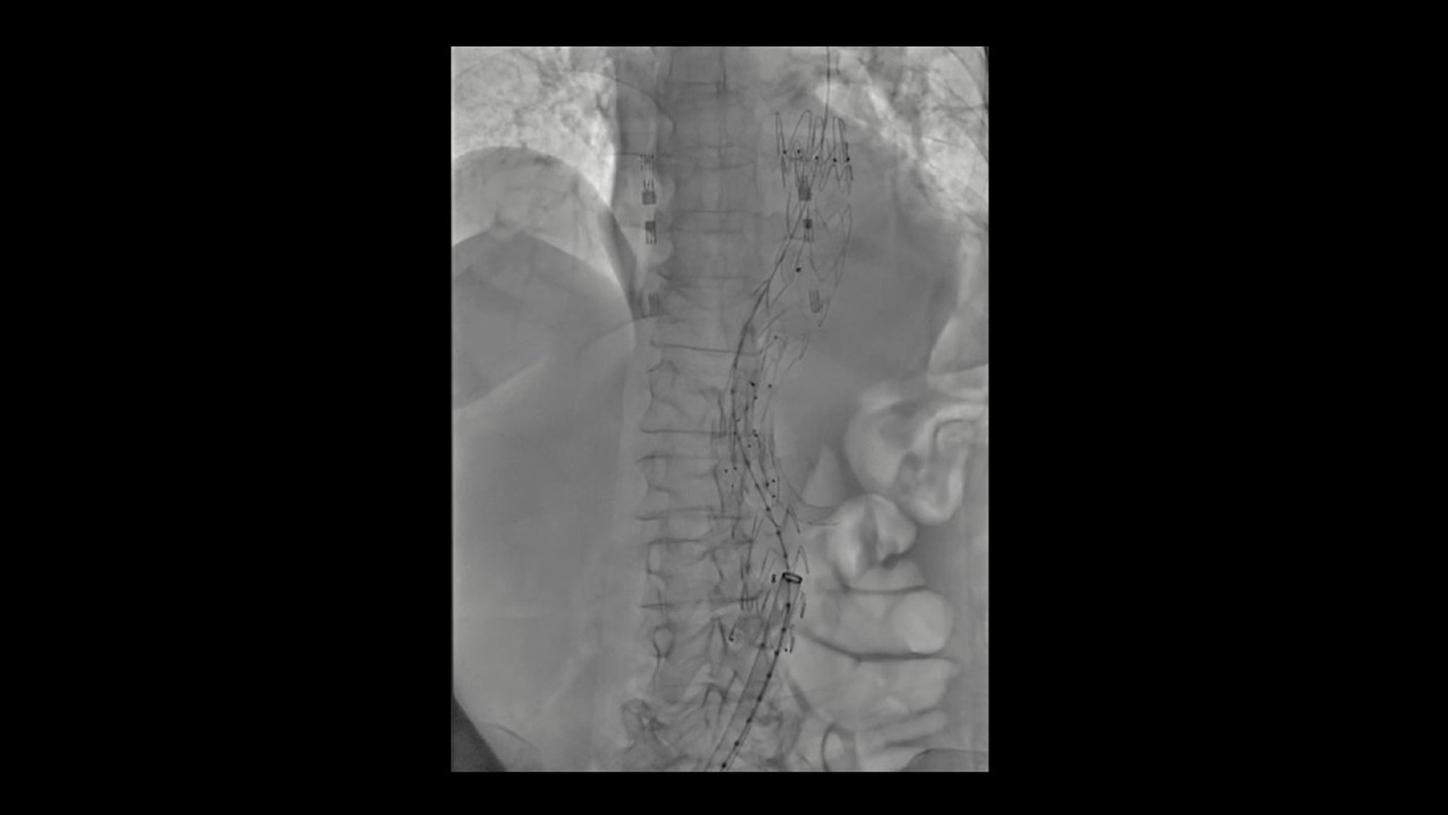

During minimally invasive procedures, it is critical to have a clear view of anatomies and devices. Yet complex imaging tasks or challenging patient conditions often impact image quality. OPTIQ AI delivers constant image quality1 defined by CNR in support of the ALARA principle, independent of patient or C-arm angulation. On top, an AI-powered algorithm reduces image noise in real time across different 2D imaging modes.

Make AI-powered imaging and clear insights your standard during interventions – with OPTIQ AI.

Future-focused IR imaging for a broad procedure mix

Discover how leading clinicians are transforming interventional radiology with Siemens Healthineers technologies. From ultra-fast 3D imaging to laser-guided needle procedures, the ARTIS icono ceiling powered by OPTIQ and syngo DynaCT are redefining what’s possible in IR. Explore real-world cases, expert insights, and the future of image-guided therapy.